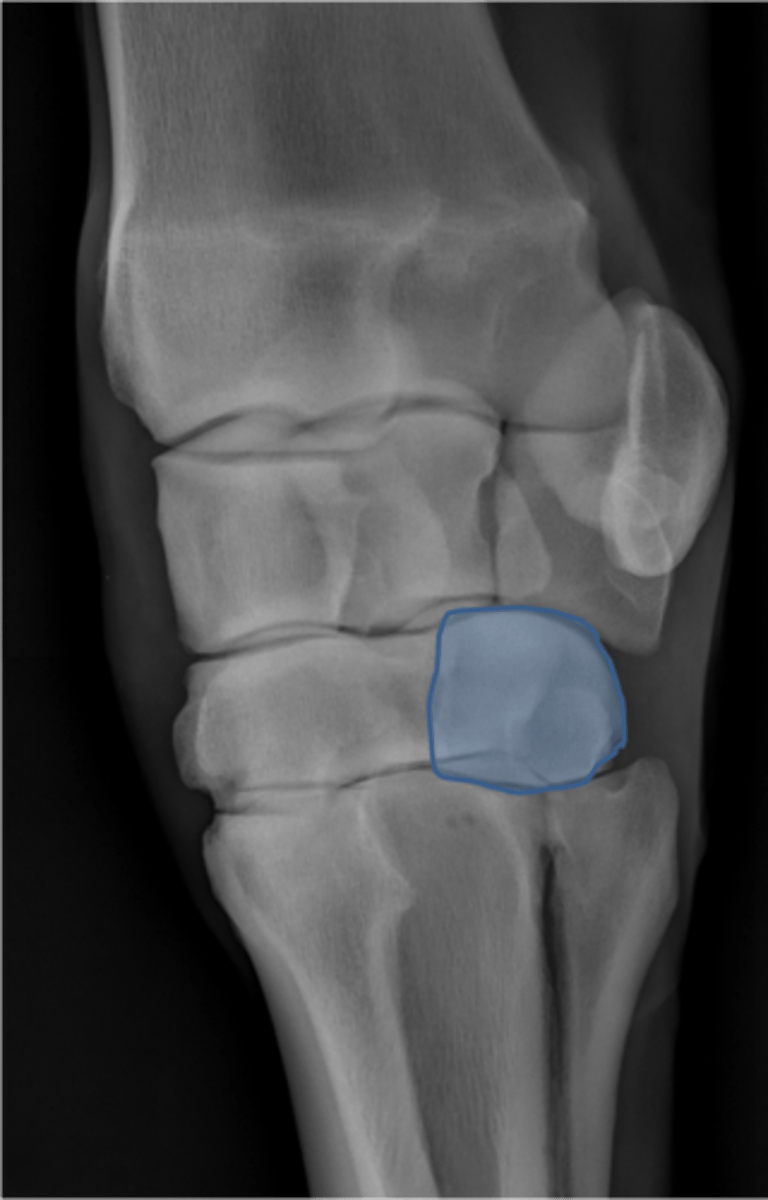

Radial carpal bone

Intermediate carpal bone

Ulnar carpal bone

Third carpal bone

Second carpal bone

Fourth carpal bone

Accessory carpal bone

Second metacarpal (medial splint)

Fourth metacarpal (lateral splint)

Cannon bone

Carpus, DP

ID joint and view

Accessory carpal bone

Radial carpal bone

Intermediate carpal bone

Ulnar carpal bone

Second carpal bone

Third carpal bone

Fourth carpal bone

Second metacarpal (medial splint)

Third metacarpal

Fourth metacarpal (lateral splint)